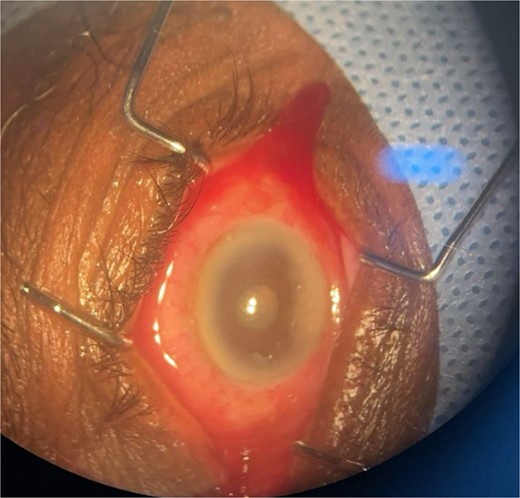

Patient 2: A 69-year-old Saudi female experienced severe right eye pain after surgery on the same day as patient 1. Visual acuity was reduced to hand motions, and examination showed conjunctival ciliary injection, corneal edema, and hypopyon (Fig. 3). B-scan confirmed vitritis (Fig. 4). She received similar emergency interventions as patient 1.

Surgical microscope examination showing hypopyon, chemosis, ciliary, and conjunctival injection in patient 2.